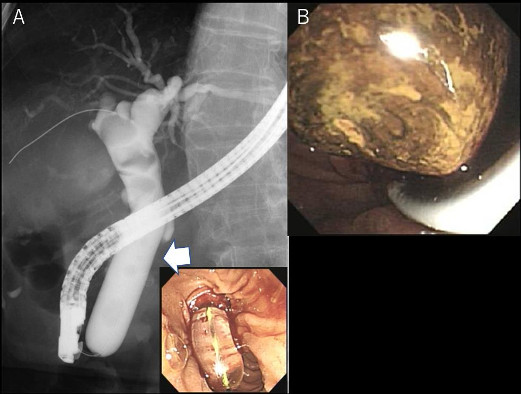

図2 内視鏡的乳頭大口径バルーン拡張術

A; 透視画像。矢印がEPLBDバルーン。右下は内視鏡画像。

B; 巨大な胆管結石を内視鏡的に除去した。